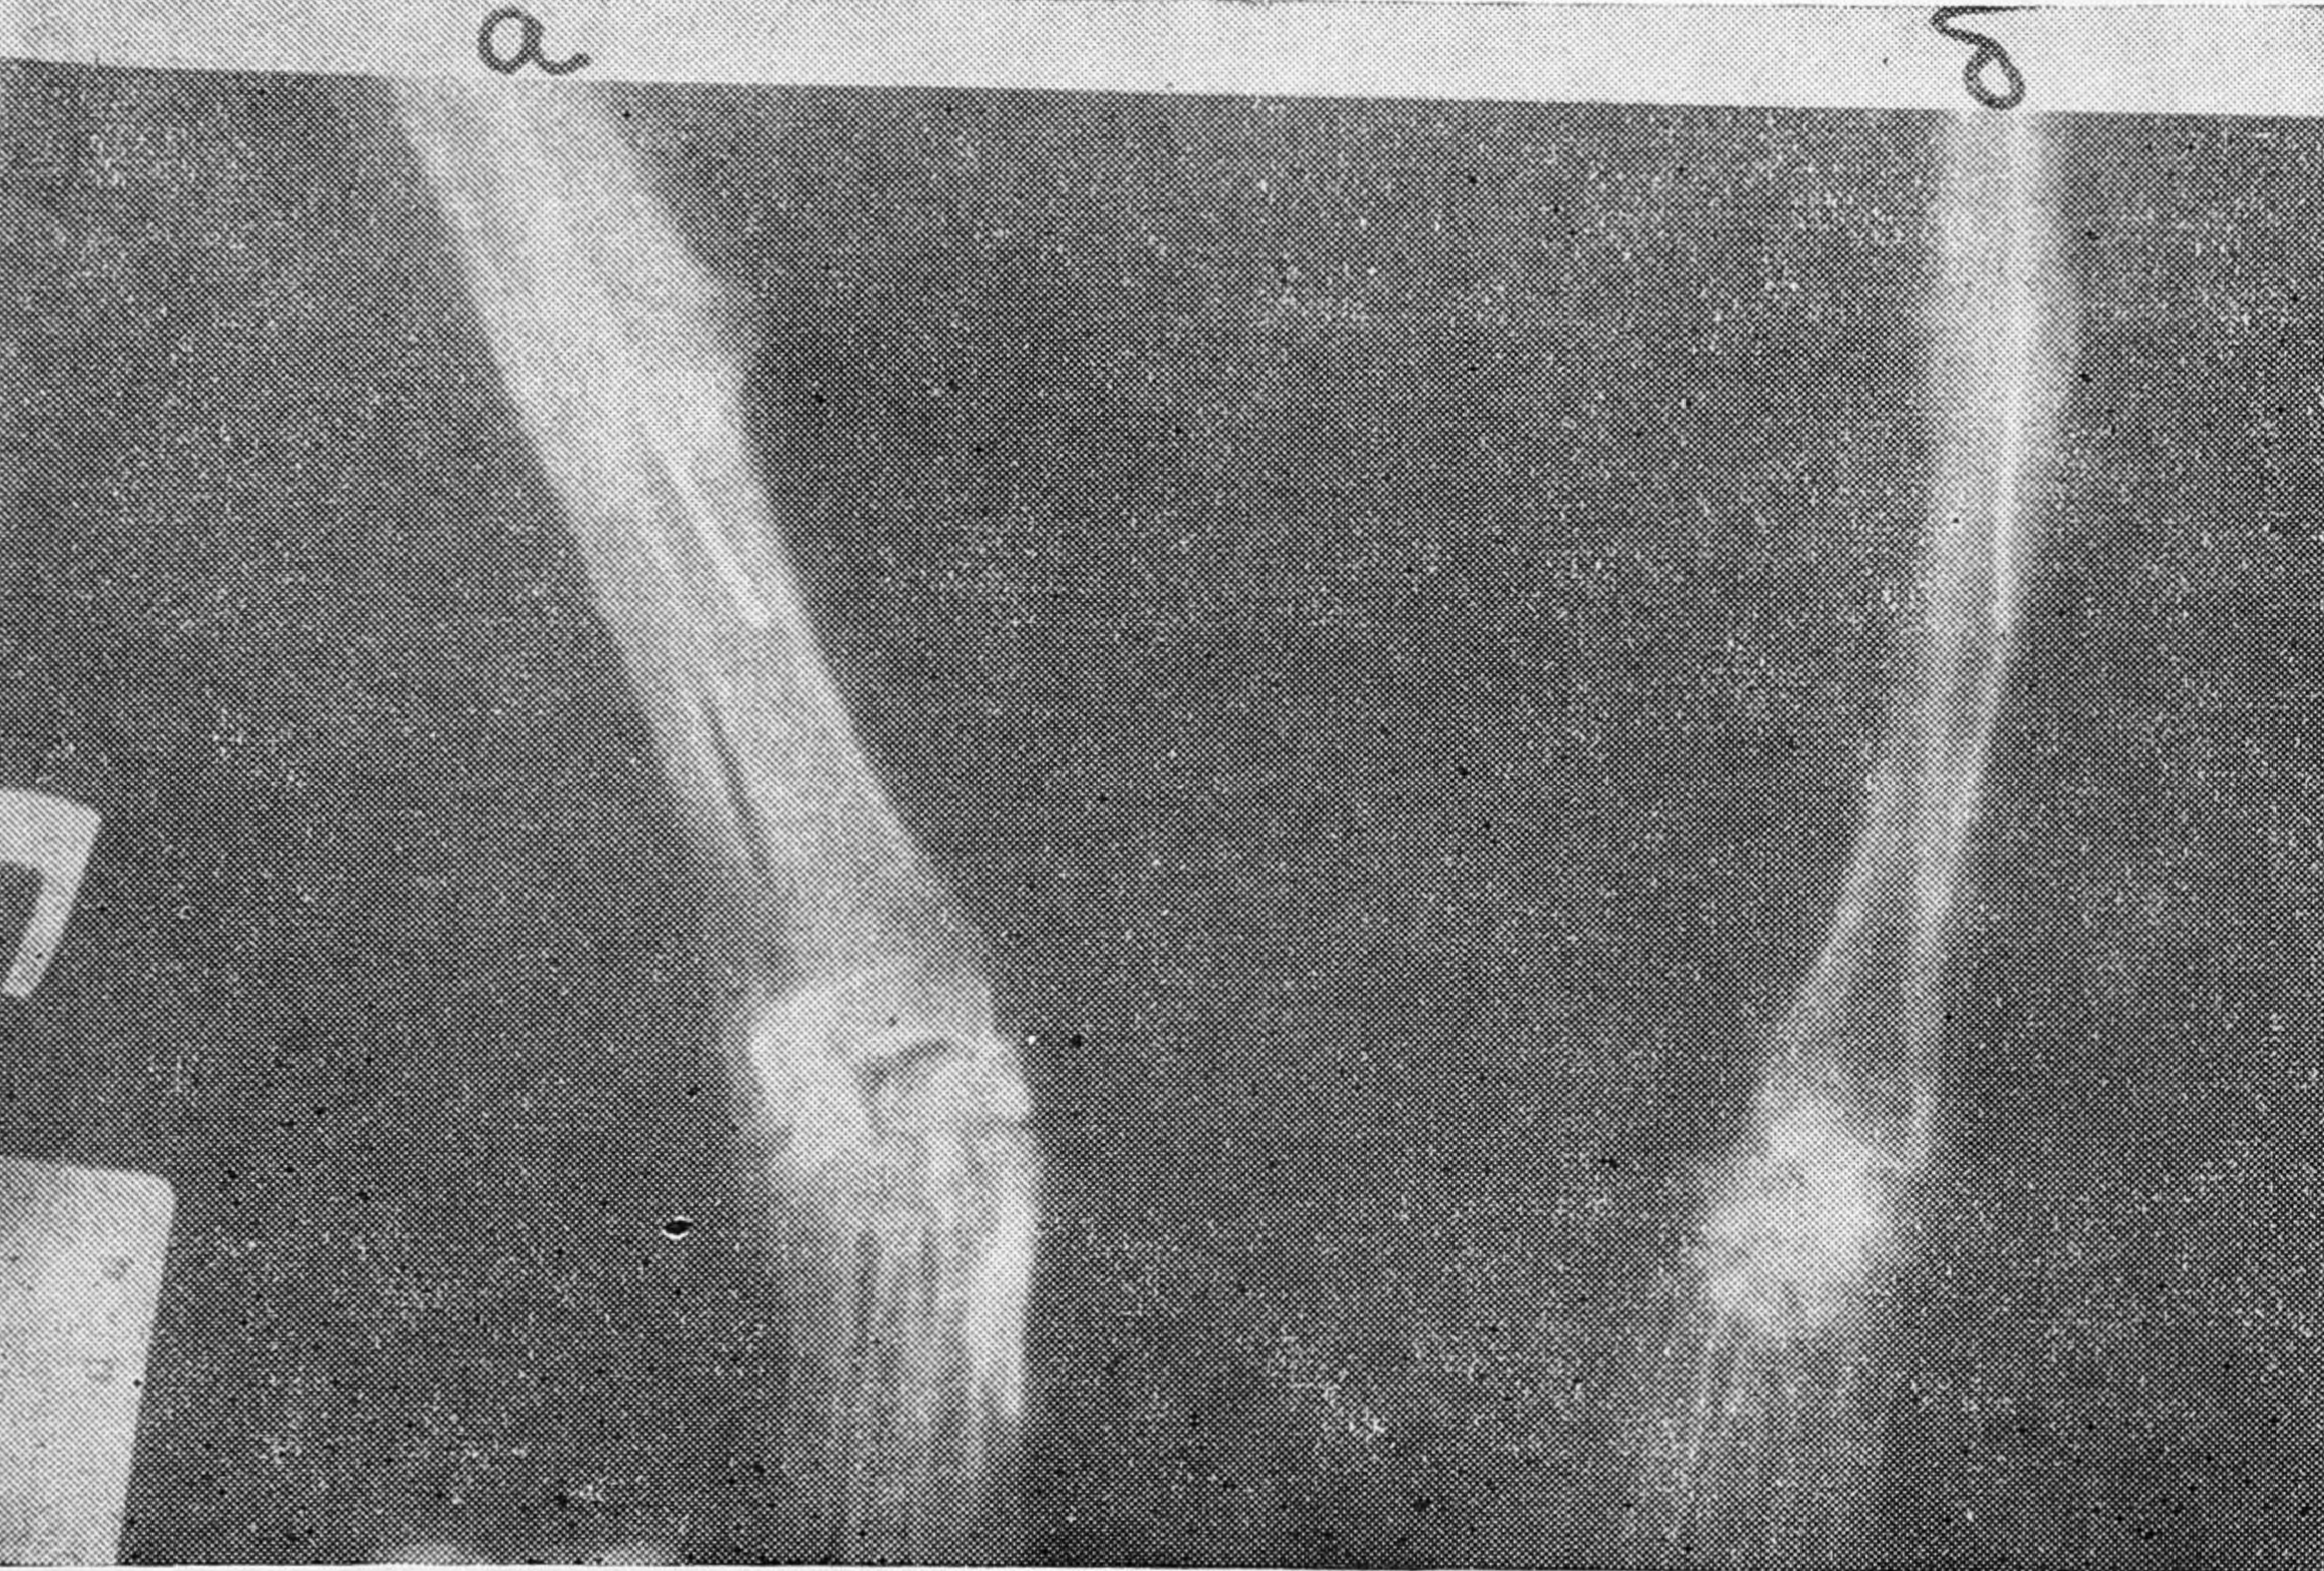

При рентгенологическом исследовании в зоне декортикации выявлена выраженная остеопластическая реакция — утолщение и разрастание остеопериостальных лоскутов. На стыках трансплантата с материнской костью идет эндостальное мозолеобразование (рис. 3).

Рис. 3. Рентгенограммы обоих предплечий собаки через месяц после костной гомопластики дефекта лучевой кости.

а — без декортикации, б — с декортикацией.

Формирующийся в области декортикации оссификат к 3 месяцам мощной муфтой охватывает трансплантат и концы материнской кости. К 6 месяцам в области трансплантации видна плотная костная мозоль. Границы трансплантата почти неразличимы. Через 8—10 месяцев в костной мозоли четко дифференцируются кортикальный слой и костномозговой канал, непрерывность которого восстановлена полностью. Края трансплантата совершенно неразличимы. Через год замещенный участок кости приобретает нормальную структуру. Имеется лишь разница в очертании контуров и плотности костного вещества в области костной мозоли по сравнению с соседними участками кости (рис. 4).

Рис. 4. Рентгенограммы обоих предплечий той же собаки через 1 год после операции.